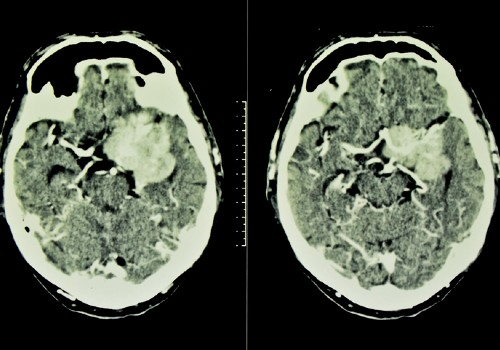

A generic image of a CT scan showing a meningioma, brain tumour